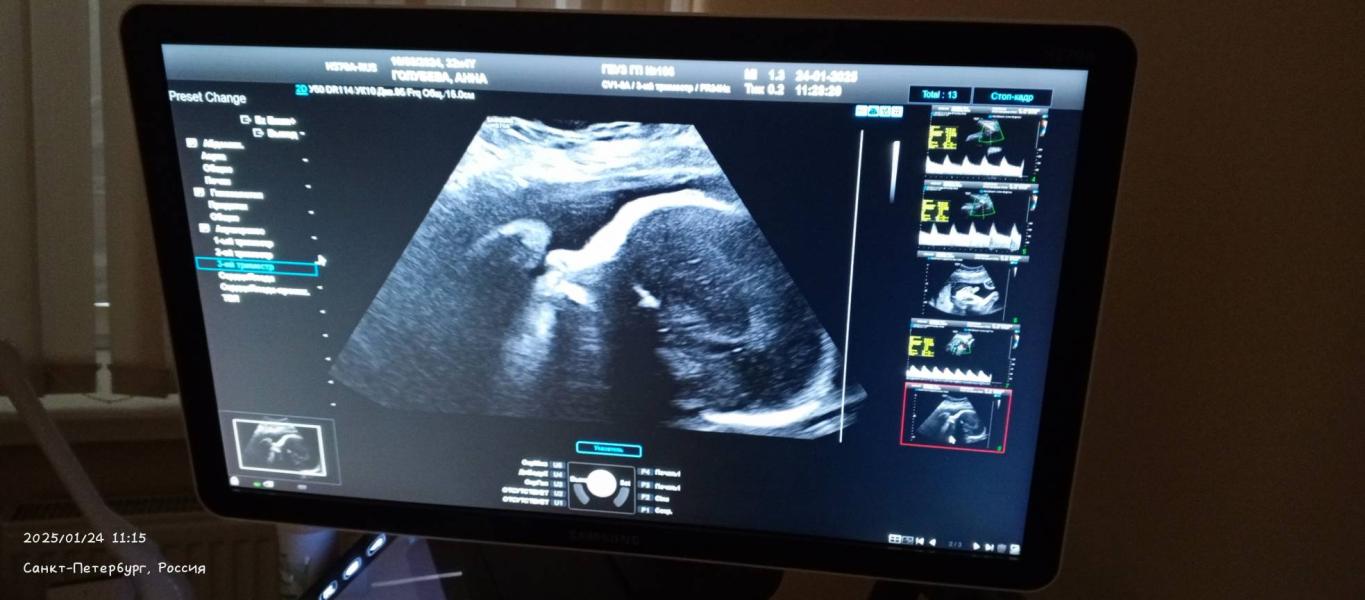

Третий скрининг: все хорошо! У нас будет мальчик, но личико малыша так и не увидели

Здравствуйте, девушки! Сегодня я была на третьем скрининге, и у нас всё хорошо. Да, мы ждём мальчика, и я очень этому рада. Я хотела посмотреть на его личико, но он не захотел его показывать.